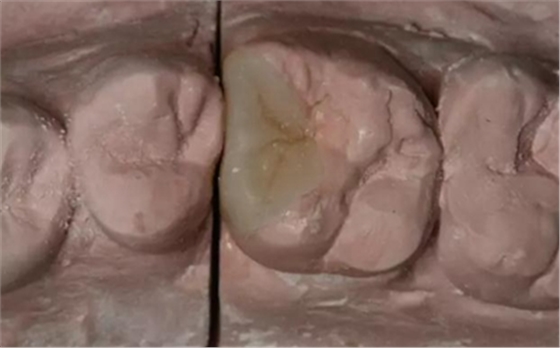

患牙遠(yuǎn)中邊緣嵴完整,強度沒有降低,故擬保留遠(yuǎn)中邊緣嵴,高嵌體修復(fù)。首先去除腐質(zhì)及原墊底材料,流體樹脂+3M Z350XT樹脂墊底。局麻下行冠延長手術(shù)。在此需要提及個人的一個觀點。冠延長手術(shù)原則上要求3-6個月以上才能永久修復(fù)。但是個人喜歡后牙肩臺建立在齦上,所以修復(fù)后的修復(fù)體邊緣位于牙齦上方1mm,對牙周的愈合影響較小(如果為齦下邊緣則要慎重),故該患者術(shù)中按照齦上邊緣的設(shè)計進行冠延長手術(shù)。以下為術(shù)中:

改良垂直褥式縫合關(guān)閉傷口,傷口無明顯滲血,高嵌體預(yù)備完畢后,硅橡膠取模,見邊緣清晰。灌注模型,模型上3MZ350XT分層堆塑高嵌體。